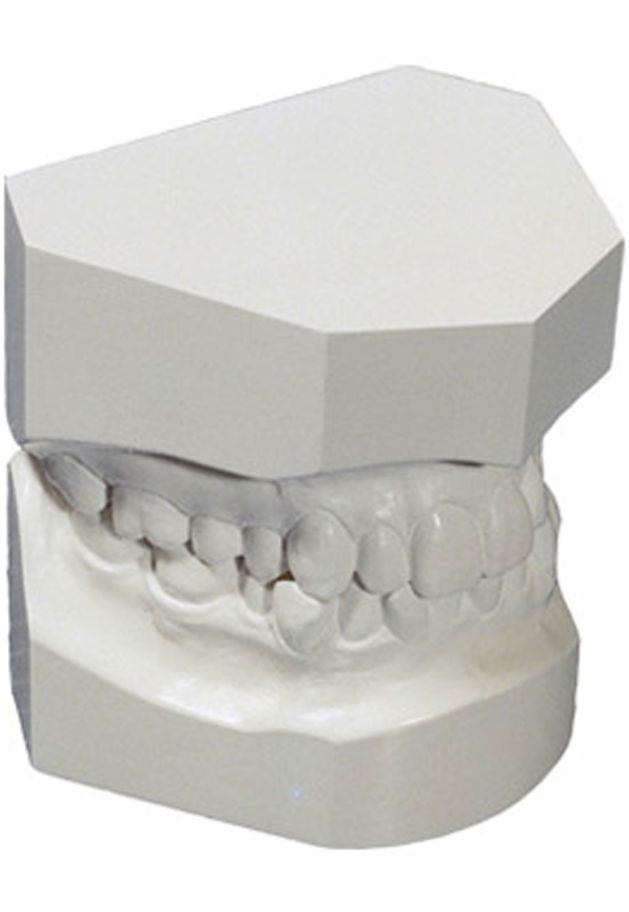

ΑΞΙΟΛΟΓΗΣΗ ΔΙΑΓΝΩΣΤΙΚΩΝ ΕΚΜΑΓΕΙΩΝ ΜΕΛΕΤΗΣ

Τα εκμαγεία μελέτης αποτελούν ομοιώματα των δοντιών του ασθενούς και δίνουν την δυνατότητα στον Ορθοδοντικός να πραγματοποιείσει μετρήσεις που τον βοηθούν να αξιολογήσει για παράδειγμα εάν ένα οδοντικό τόξο είναι στενό ή ευρύ, εάν υπάρχει έλλειψη χώρου ή υπάρχει χώρος για να ανατείλουν τα μόνιμα δόντια, εάν υπάρχει δυσαρμονία μεγέθους δοντιών μεταξύ του άνω και του κάτω οδοντικού τόξου κ.α.